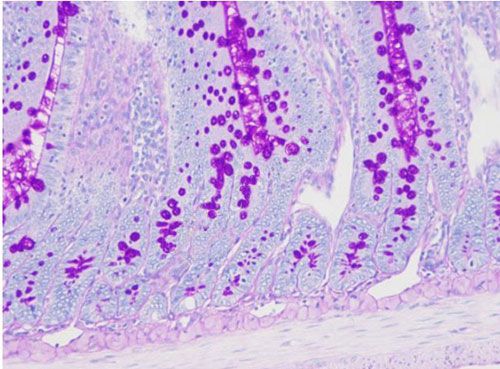

PAS染色又稱過(guò)碘酸雪夫染色,糖原染色。一般用來(lái)顯示糖元和其它多糖物質(zhì)。過(guò)碘酸能使細(xì)胞內(nèi)的多糖乙二醇基氧化成二醛,再與Schiff氏液的無(wú)色品紅結(jié)合,紅色,定位于胞漿上

實(shí)驗(yàn)結(jié)果展示:

PAS染色—小鼠腸

糖原、中性粘液物質(zhì)、軟骨基質(zhì)、植物的真菌和細(xì)胞壁、上皮的基膜等均呈紫紅色,細(xì)胞核淺藍(lán)色